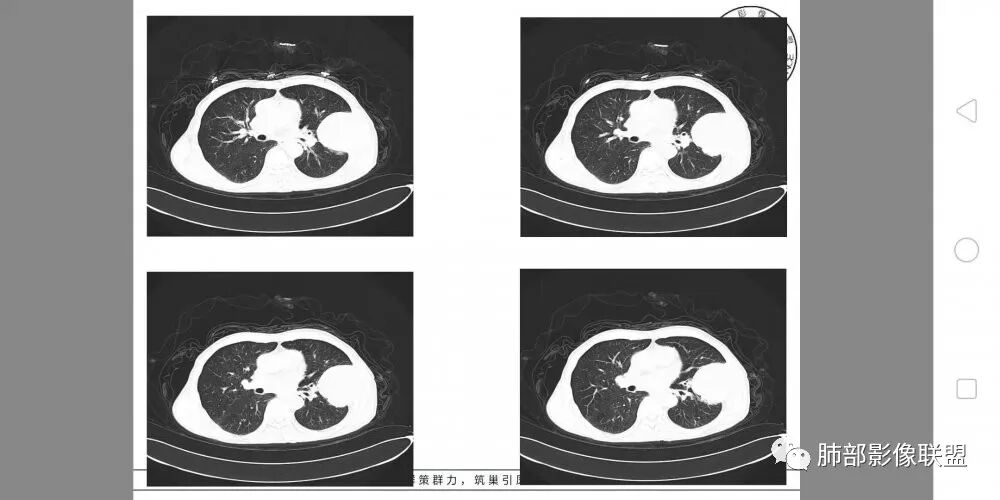

一切∮随缘

左肺上叶下舌段胸膜下肿块,宽基底与胸膜相连,尖端指向肺门,病变呈膨胀性生长,边缘有清晰的GGO,病灶下缘似有空泡,病灶外缘向胸壁外侵犯(有栽赃),局部肋骨有破坏,平扫密度均匀,增强后轻度强化,中老年男性,有外伤史,考虑恶性,神经鞘瘤,恶性肉瘤,恶性孤立性纤维瘤,鉴别血肿(强化不太符合)

淘时光

左肺上叶占位,支气管无明显阻塞,上下舌段支气管受压推移为主,分叉角增大,胸壁受侵犯,肋骨骨质破坏,考虑肺内外朝内的病变,肉瘤样癌?

定位,肺内,左肺上叶胸膜下肿块,边缘光滑,未见分叶毛刺,支气管受压推移,有大片坏死,胸壁受侵犯,考虑恶性,肉瘤样癌?可以多平面重建看支气管跟肺内关系,如果支气管有截断,不除外磷癌

胸部CT所见左肺上叶尖后段胸膜下较大山丘形肿块,边界清楚,宽基底与胸膜相贴,边缘与胸膜呈直角及锐角相交。邻近上叶尖后段支气管受压推挤,叶裂局部膨隆,病灶周围见少许磨玻璃密度影,边界不清。纵膈窗显示,肿块密度均匀,增强扫描呈不均匀轻度强化,邻近肋骨骨质破坏,病变沿肋间隙向外侵犯,局部胸膜增厚。纵膈内见多发小淋巴结,未见胸腔积液征象。综合考虑恶性占位,肉瘤样癌可能性大。腰椎及髋部考虑骨转移。

毛勤香 广西柳州龙潭医院影像

老年男性,左肺上叶舌段胸膜下肿块,外朝内生长,对应支气管受压变窄,肿块边界清晰,邻近胸膜胸壁和肋骨受侵犯,增强扫描明显不均匀强化,内有较多坏死,考虑恶性,首先肉瘤样癌,鉴别低分化腺癌。